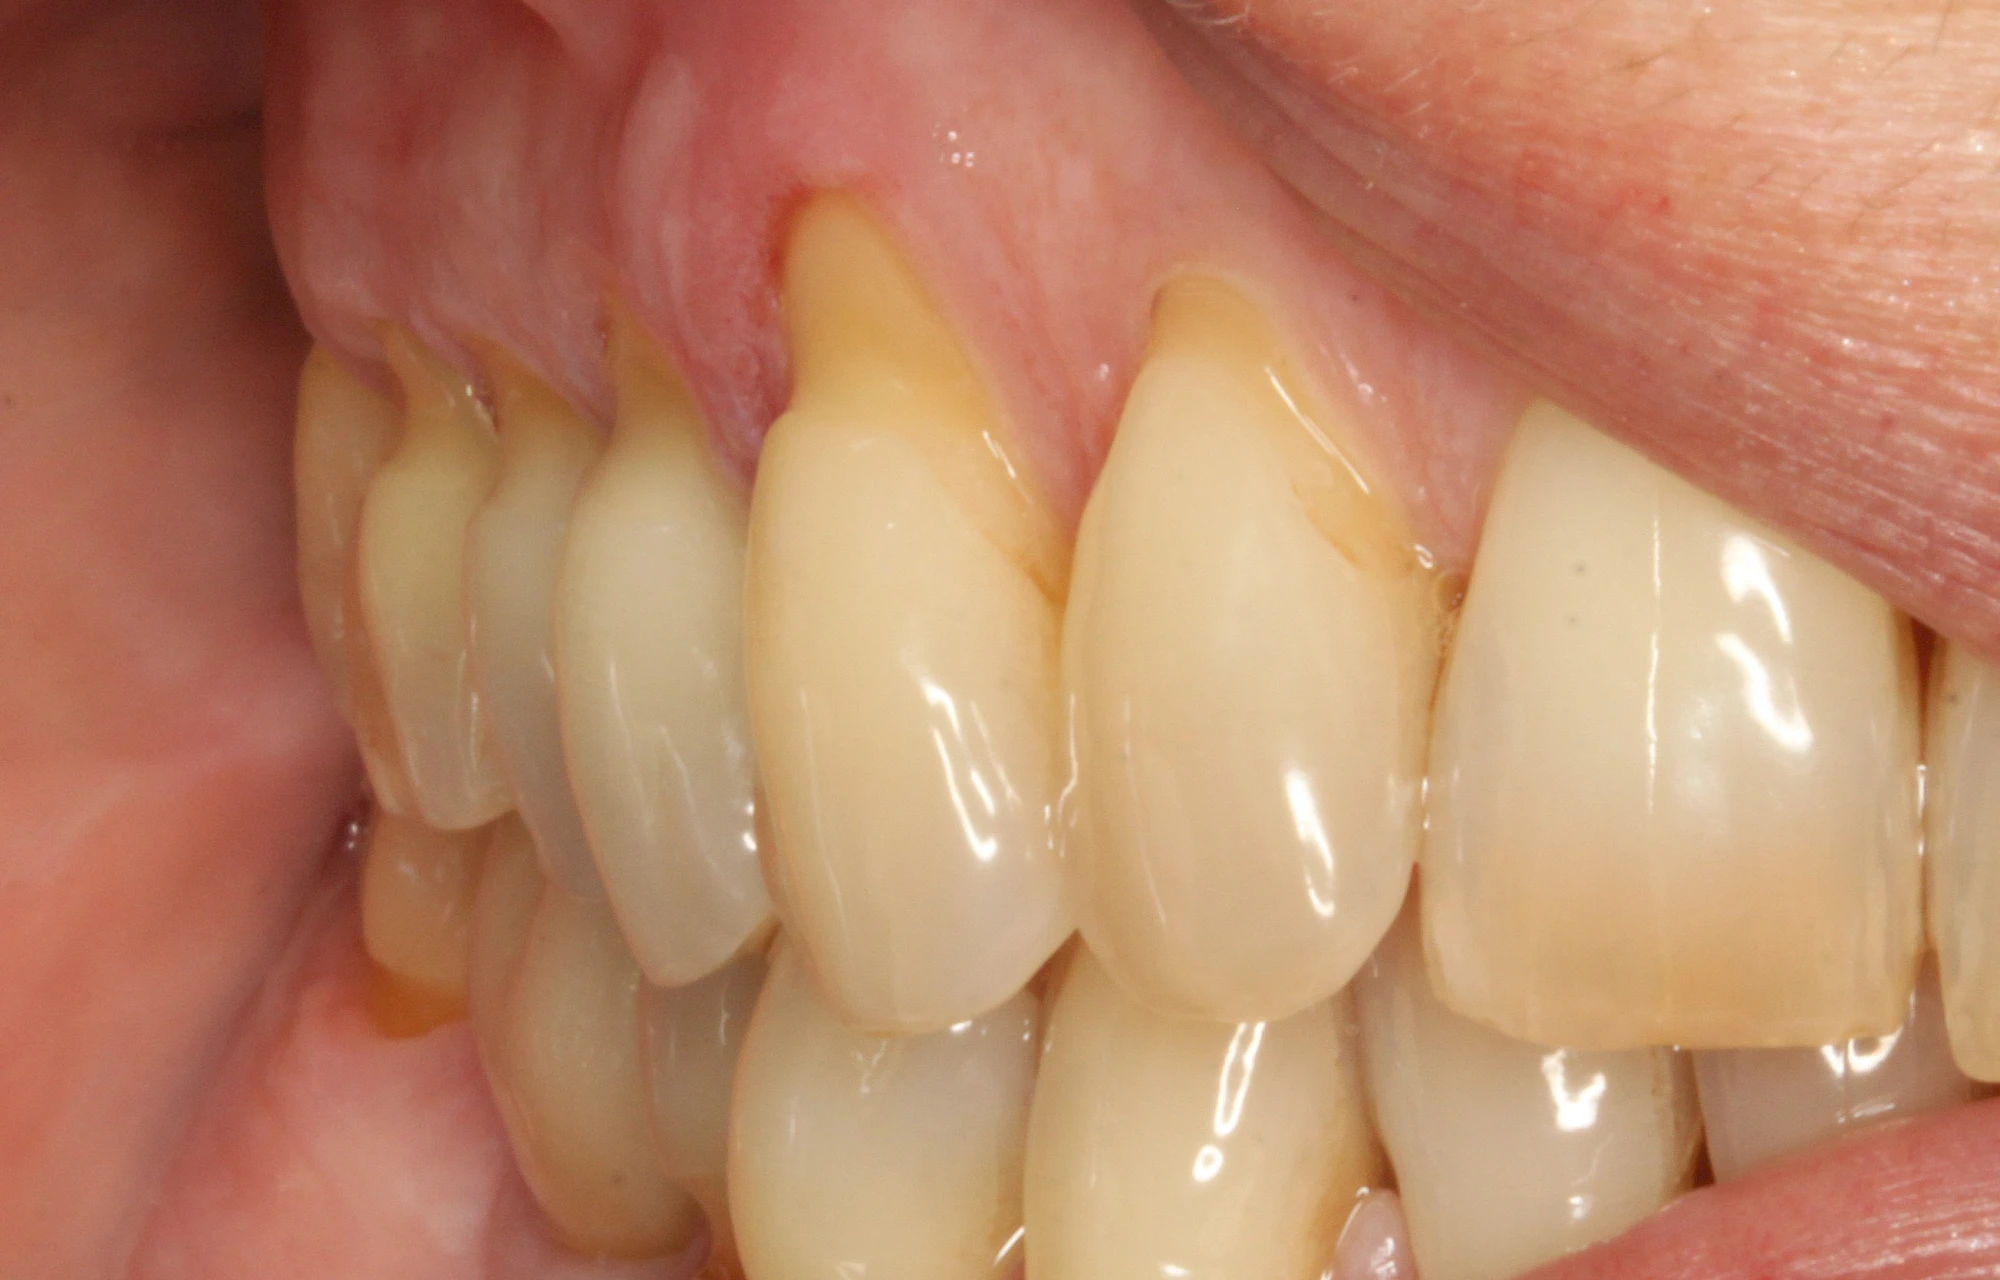

Keilförmiger Defekt

Eine Sonderform sind sogenannte keilförmige Defekte im Bereich der Zahnhälse. Hier geht man davon aus, dass Knirschen und Pressen in Kombination mit falschen Putzgewohnheiten (zu hoher Putzdruck, Verwendung von Zahnpasta mit hohen Abrasionswerten) eine Rolle spielen.